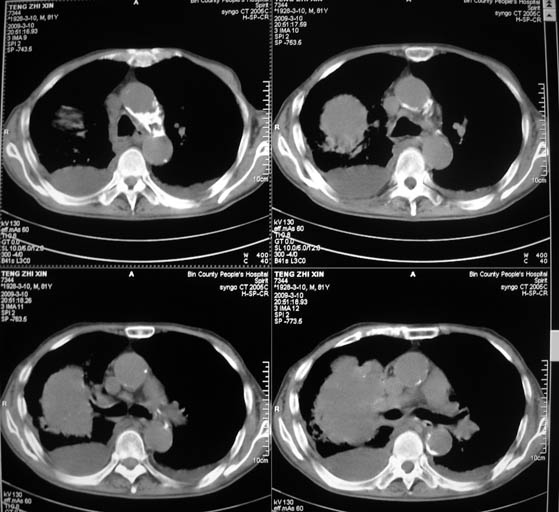

标题: CT18642:男,81岁,发热待查。

男,81岁,发热待查,右侧是占位还是膈疝?

1)考虑右肺下叶中央型肺癌并左肺转移。2)两肺上叶结核(陈旧性)。3)双侧胸腔积液。4)腹水。

右肺癌并双肺及胸膜转移。

右中央型肺癌并双肺及胸膜、肝脏转移